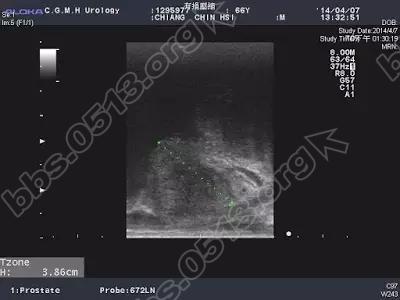

江先生,69岁男性,大约10年前已经接受过一次前列腺电切手术,刚开始尿的还不错。经过两三年后,排尿症状就又开始不好,排尿要先等一会才开始尿、腹部需要用力、憋尿后反而尿不出来、有时一尿急,来不及跑到厕所马上就尿在裤子上了,所以第一次开完刀后没有三五年后又开始与前列腺肥大药物为伍,也因为药物效果越来越差,江先生来到医院寻求协助, 前列腺彩超方面,体积勉强达到前列腺肥大的标准、看起来仅轻微突入到膀胱内、之前切除的沟槽也已经看不到了,但解尿的尿流速图形及残尿,显示还是有阻塞。